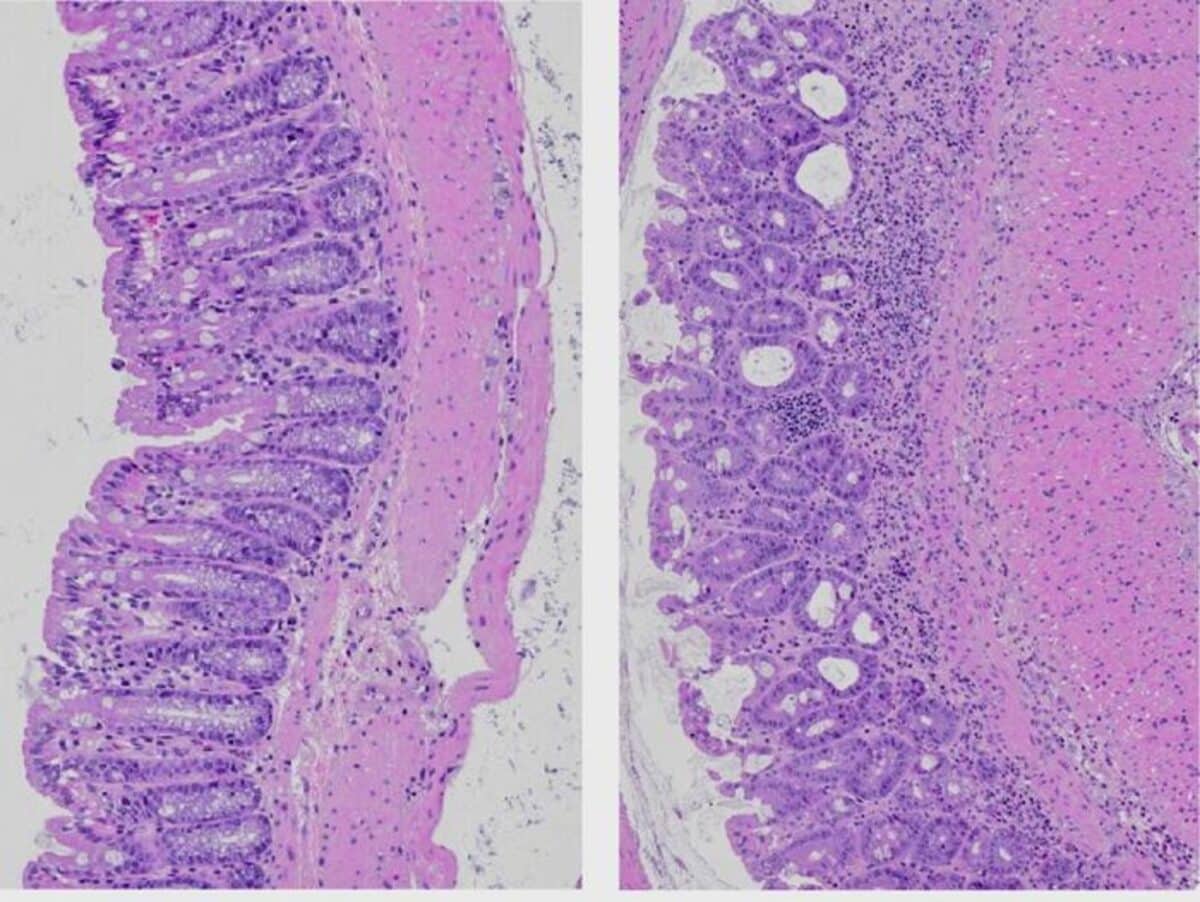

To investigate these effects, the scientists fed mice different diets for varying periods. Some received regular chow, while others consumed food with 36% or 60% fat content. The researchers observed that after just two days on high-fat diets, certain subtypes of ILC3 immune cells already showed reduced IL-22 production. By day seven, all ILC3 subtypes were compromised.

This dietary change simultaneously triggered rapid shifts in the gut microbiome, the community of bacteria living in our intestines. Within a week, beneficial bacteria that produce short-chain fatty acids declined, while potentially harmful species increased. Some of these harmful bacteria, like Enterococcus gallinarum, are known to reduce intestinal mucus and damage the connections between gut cells.

Using specialized equipment to measure different factors in the intestines, the researchers confirmed that after just one week on a high-fat diet, the mice’s intestines became measurably “leakier,” allowing more substances to pass through that would normally be kept out.

Within 48 hours of high-fat diet exposure, mice showed impaired IL-22 production by ILC3s, which became more pronounced by day 7. This coincided with increased gut permeability, decreased expression of antimicrobial peptides, mucus, and tight junction proteins. The gut microbiome rapidly shifted, with beneficial bacteria declining and potentially harmful species increasing. When mice returned to a regular diet, these changes were largely reversed within 7 days. Importantly, saturated and unsaturated fatty acids had opposing effects. Saturated fats like palmitic acid reduced IL-22 production through fat oxidation pathways, while unsaturated fats like oleic acid maintained IL-22 production by forming protective lipid droplets in immune cells. When inflammation was induced, mice fed saturated fat diets showed worse outcomes than those on unsaturated fat or regular diets. Similar effects were observed in human immune cells exposed to different fatty acids.